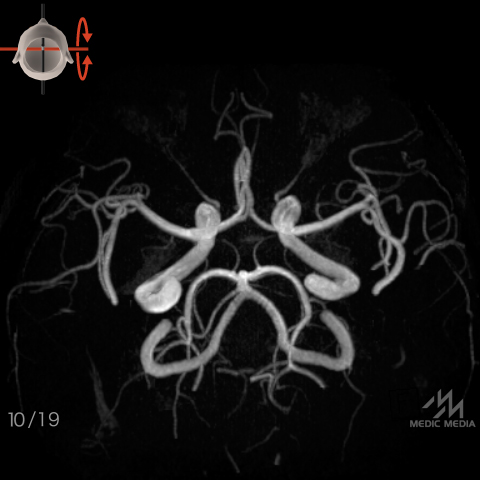

脳動脈(MRA像)

スライド(画像下)を動かし脳動脈の解剖を確認しましょう.

前後軸回転

動脈名表示

動脈名表示+色分け